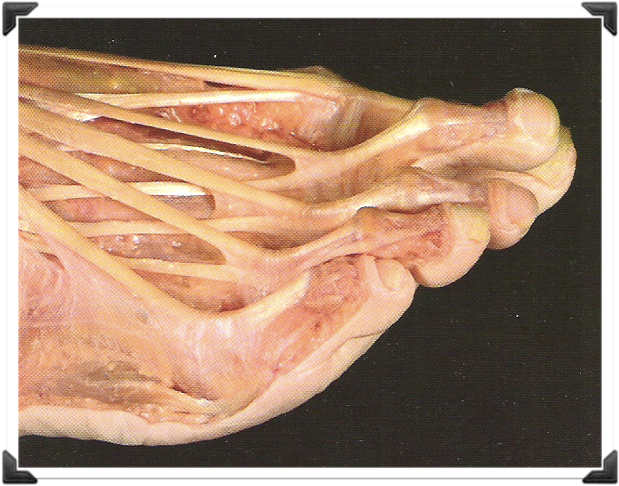

Principios de la Técnica

Corrección en el ápice o ángulo de la deformidad

Fijación Dinámica Blanda

- Fracturas Múltiples

- Osteotomías

- Liberación de Partes Blandas (Contractura)

- Tenotomías y Capsulotomías

- Realineación Anatómica

- Vendaje Blando, protege las heridas, alineación del pie, estabilidad relativa de las osteotomías